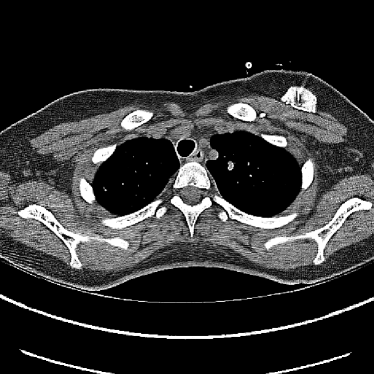

Figure 9: (a) The ACR phantom module 1 with 4 different inserts for CT number fidelity testing. In addition, two ramps of wires are visible near the phantom center. The image display window center is 150 HU and window width is 700 HU. (b) The phantom module 3 with a uniform water-equivalent radiodensity of 0 HU. The display window center is 0 HU and window width is 400 HU.

To evaluate image quality, we first tested the performance of JENG on a standard CT phantom, CT ACR 464 phantom 35. Then we tested JENG on 5 clinical thoracic datasets and 3 abdominal datasets. The ACR 464 phantom contains four modules in total, with each module 40 mm in depth and 200 mm in diameter. The first module has 4 different inserts to test CT number fidelity. In addition, the module contains a series of wires for cross-plane resolution evaluation, shown as white horizontal bars near the center in Fig. 9(a), and are visible in 0.5 mm z-axis increments. The second module tests low contrast resolution, but is not used in this paper. The third module, shown in Fig. 9(b), is a uniform cylinder of water-equivalent material of 0 Hounsfield units (HU), and we used this module to quantitatively measure image noise profile and in-plane resolution. The fourth module consists of resolution bars of various spatial frequencies for analysis on high contrast resolution. To scan the phantom, the scanner setup used dual sources with 2 focal spots at each source. In addition, the projections were acquired using the same protocol for clinical thoracic scans with 100 KV, a nominal tube current of 718 mA and a high helical pitch of 2.8. For all experiments, we compared JENG against the state-of-the-art Siemens ADMIRE, reconstructed with a BL-64 soft tissue sharp kernel, and we define ADMIRE as the clinical standard hybrid IR method for the rest of the paper.

Figure 14: Qualitative clinical results from a thoracic CT staging dataset for a 12-year-old with osteosarcoma with pulmonary metastases. The clinical standard hybrid IR is shown on the left and JENG is on the right. (a) The clinical standard hybrid IR in lung window with a window center of -600 HU and a window width of 1500 HU. (b) JENG at a resolution comparable to the clinical standard, but with less noise and fewer artifacts. (c) The clinical standard hybrid IR in soft tissue window with a window center of 55 HU and a window width of 440 HU. A metastatic lung cancer nodule can be found in the left upper lobe. (d) JENG in soft tissue window at a comparable resolution, but with less noise and fewer artifacts. Note that JENG is not fully corrected for beam hardening artifacts.